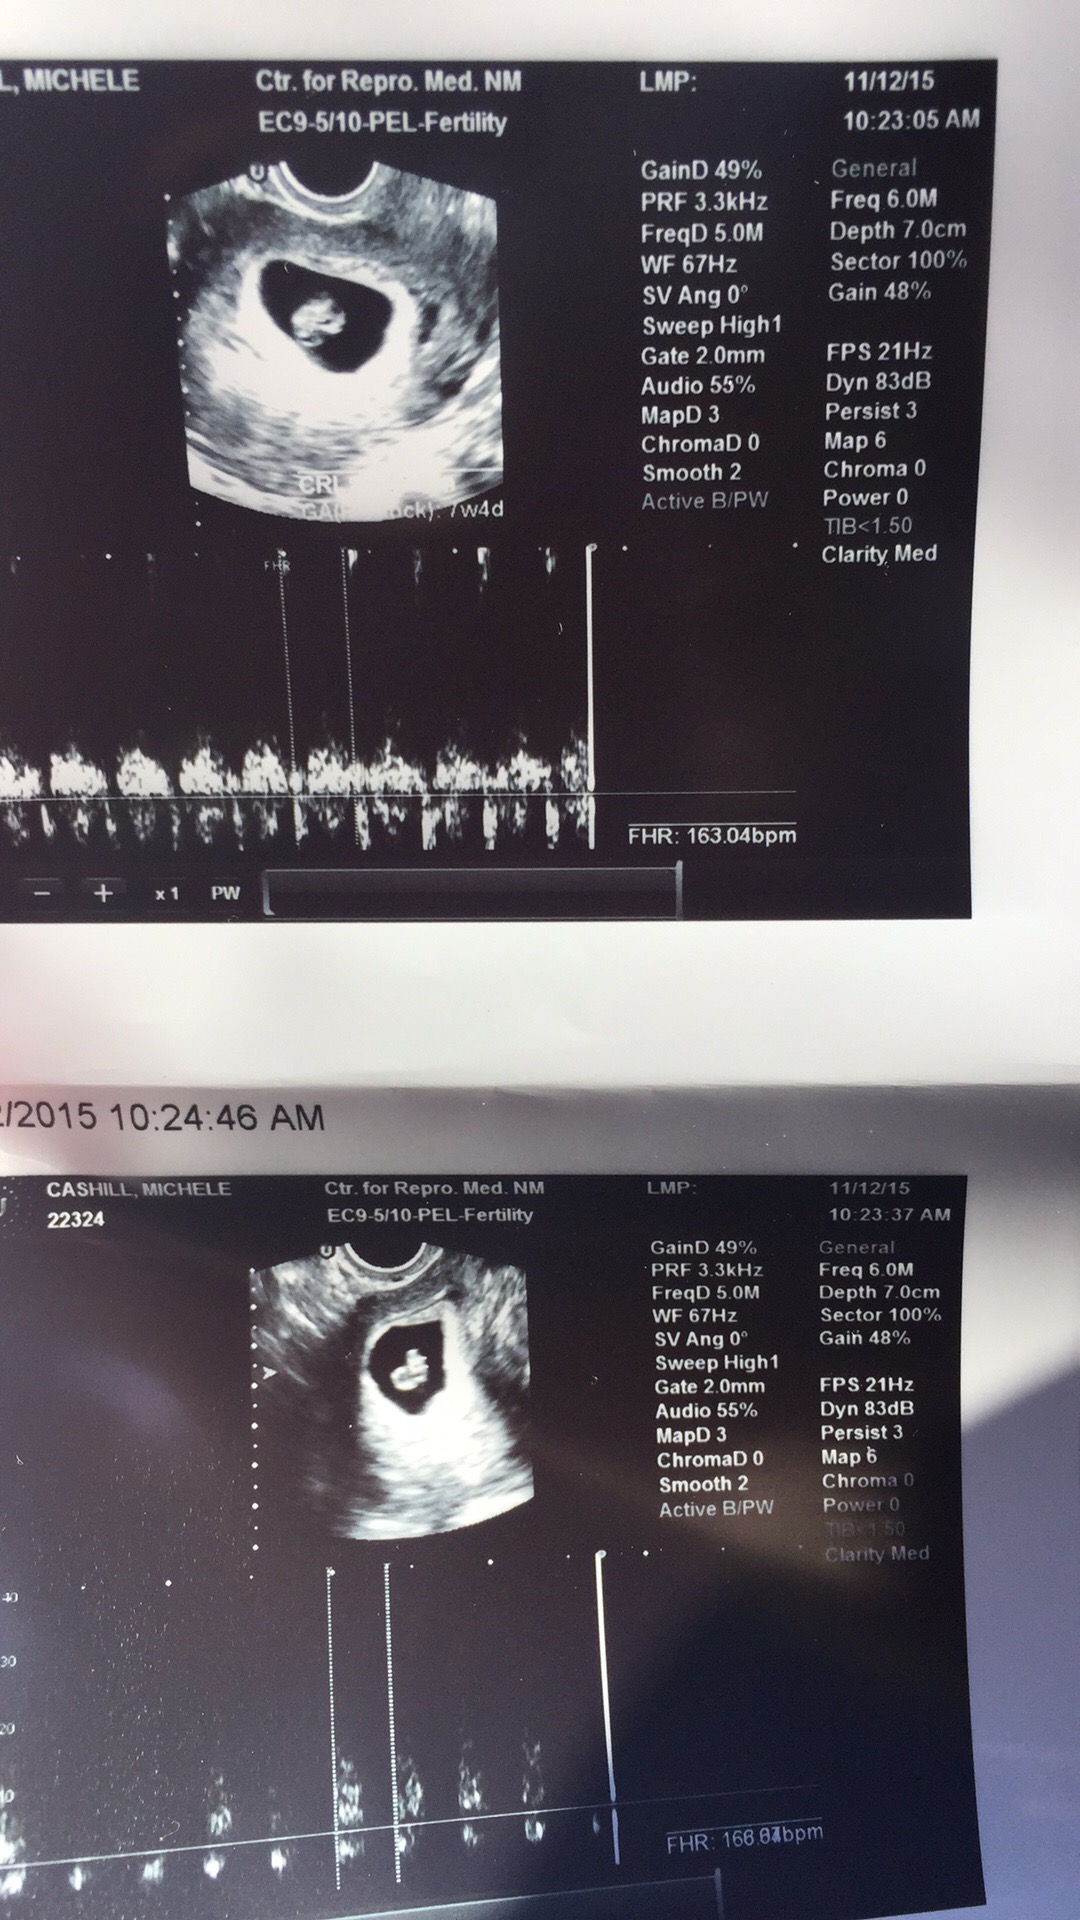

Twins!!!!!! I had two ultrasounds, one week apart.